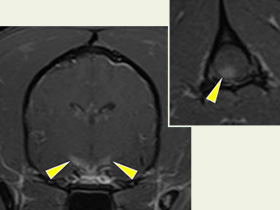

特発性脳炎症例のMRI(造影後T1強調画像)

神経学的検査、MRI検査、髄液(脳脊髄液)の細胞診によって肉芽腫性髄膜脳脊髄炎(GME)と診断し、免疫抑制剤による治療を開始した。

脳の視覚経路と脊髄に病変が認められた